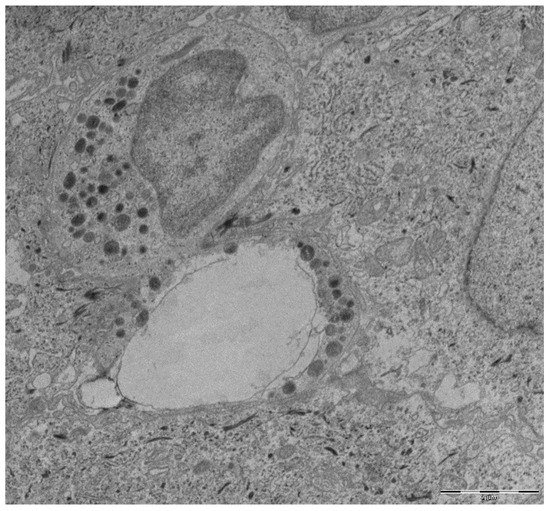

| Vitkov et al. [69] | 2009 | 22 Chronic Periodontitis | Purulent crevicular exudate (22); Gingival biopsies (12) | Exudates: NE and DNA; Biopsies: Transmission electron microscopy (TEM) and SEM (with and without DNase). | NETs were found on all the exudate samples. DNase caused the disappearance of NETs |